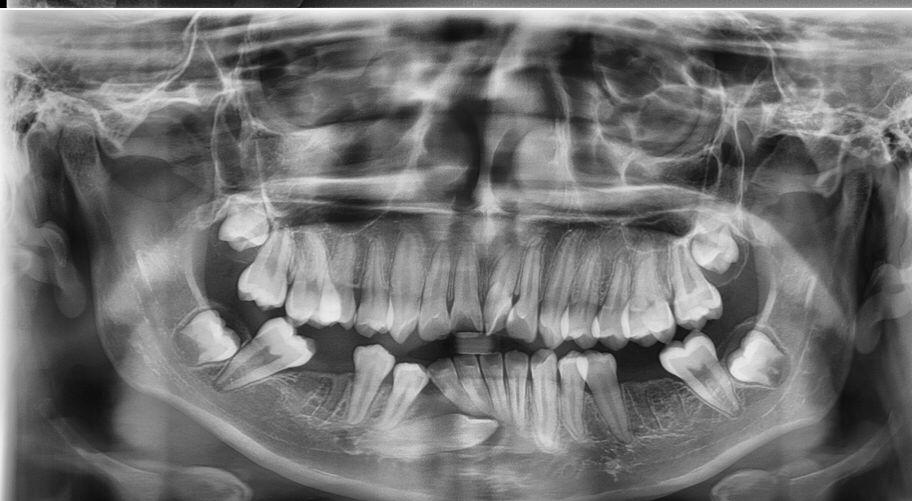

- Ortopantomografía (radiografía panorámica dental)